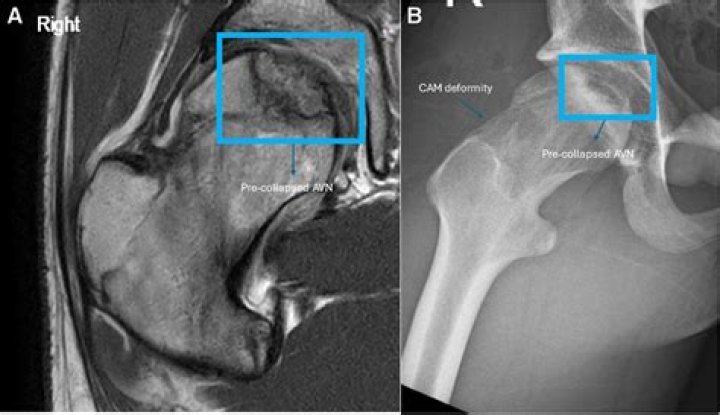

Imaging of osteonecrosis is frequently diagnostic with a serpentine rim of sclerosis on radiographs, photopenia in early disease at bone scintigraphy, and maintained yellow marrow at MR imaging with a serpentine rim of high signal intensity (double-line sign) on images obtained with long repetition time sequences.

The classic MR appearance of osteonecrosis is that of a segmental area of low signal intensity in the subchondral bone, bounded by a low signal intensity border. This border may sometimes appear as a dark line adjacent to a bright line — the so-called “double line sign”.

Stage 1 has a normal x-rays but MRI reveals the dead bone. Stage 2 can be seen on regular x-ray but there is no collapse of the femoral ball. Stage 3 shows signs of collapse (called a crescent sign) on x-ray. Stage 4 has collapse on x-ray and signs of cartilage damage (osteoarthritis).

Can you see AVN on MRI?

MRI is the most sensitive and specific means of diagnosing AVN. MRI may detect disease as early as 5 days subsequent to an ischemic insult. Characteristic MRI findings for AVN of the hip include a low signal intensity band (seen on T1 and T2 images) that demarcates a necrotic anterosuperior femoral head segment.